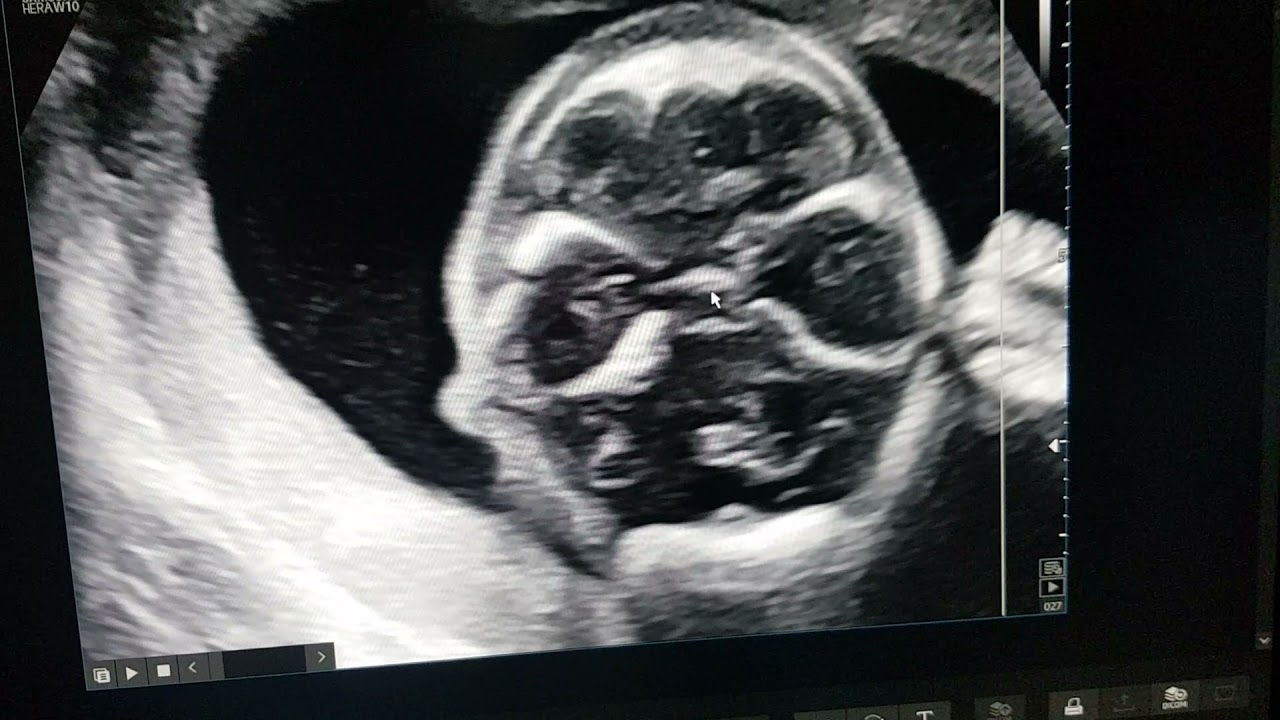

Варикозное расширение пупочной вены плода. Доктор Прадип Шринивасан, серия статей REFER SERIES, r...

Обучение фетальной сонографии в рамках серии REFER от доктора С. Прадипа: Варикозное расширение пупочной вены плода (FIUVV). (Ссылка на материалы: FIUVV.refer.mediknit.org)